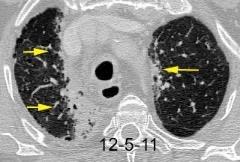

Triada de Garland

Ganglios paratraqueales derechos e hiliares bilaterales

95% de pacientes tienen ganglios hiliares bilaterales aislados o con afectación mediastínica (espec. paratraqueal derecho).

Criado E et al. Pulmonary sarcoidosis: typical and atypical manifestations at high-resolution CT with pathologic correlation. Radiographics. 2010